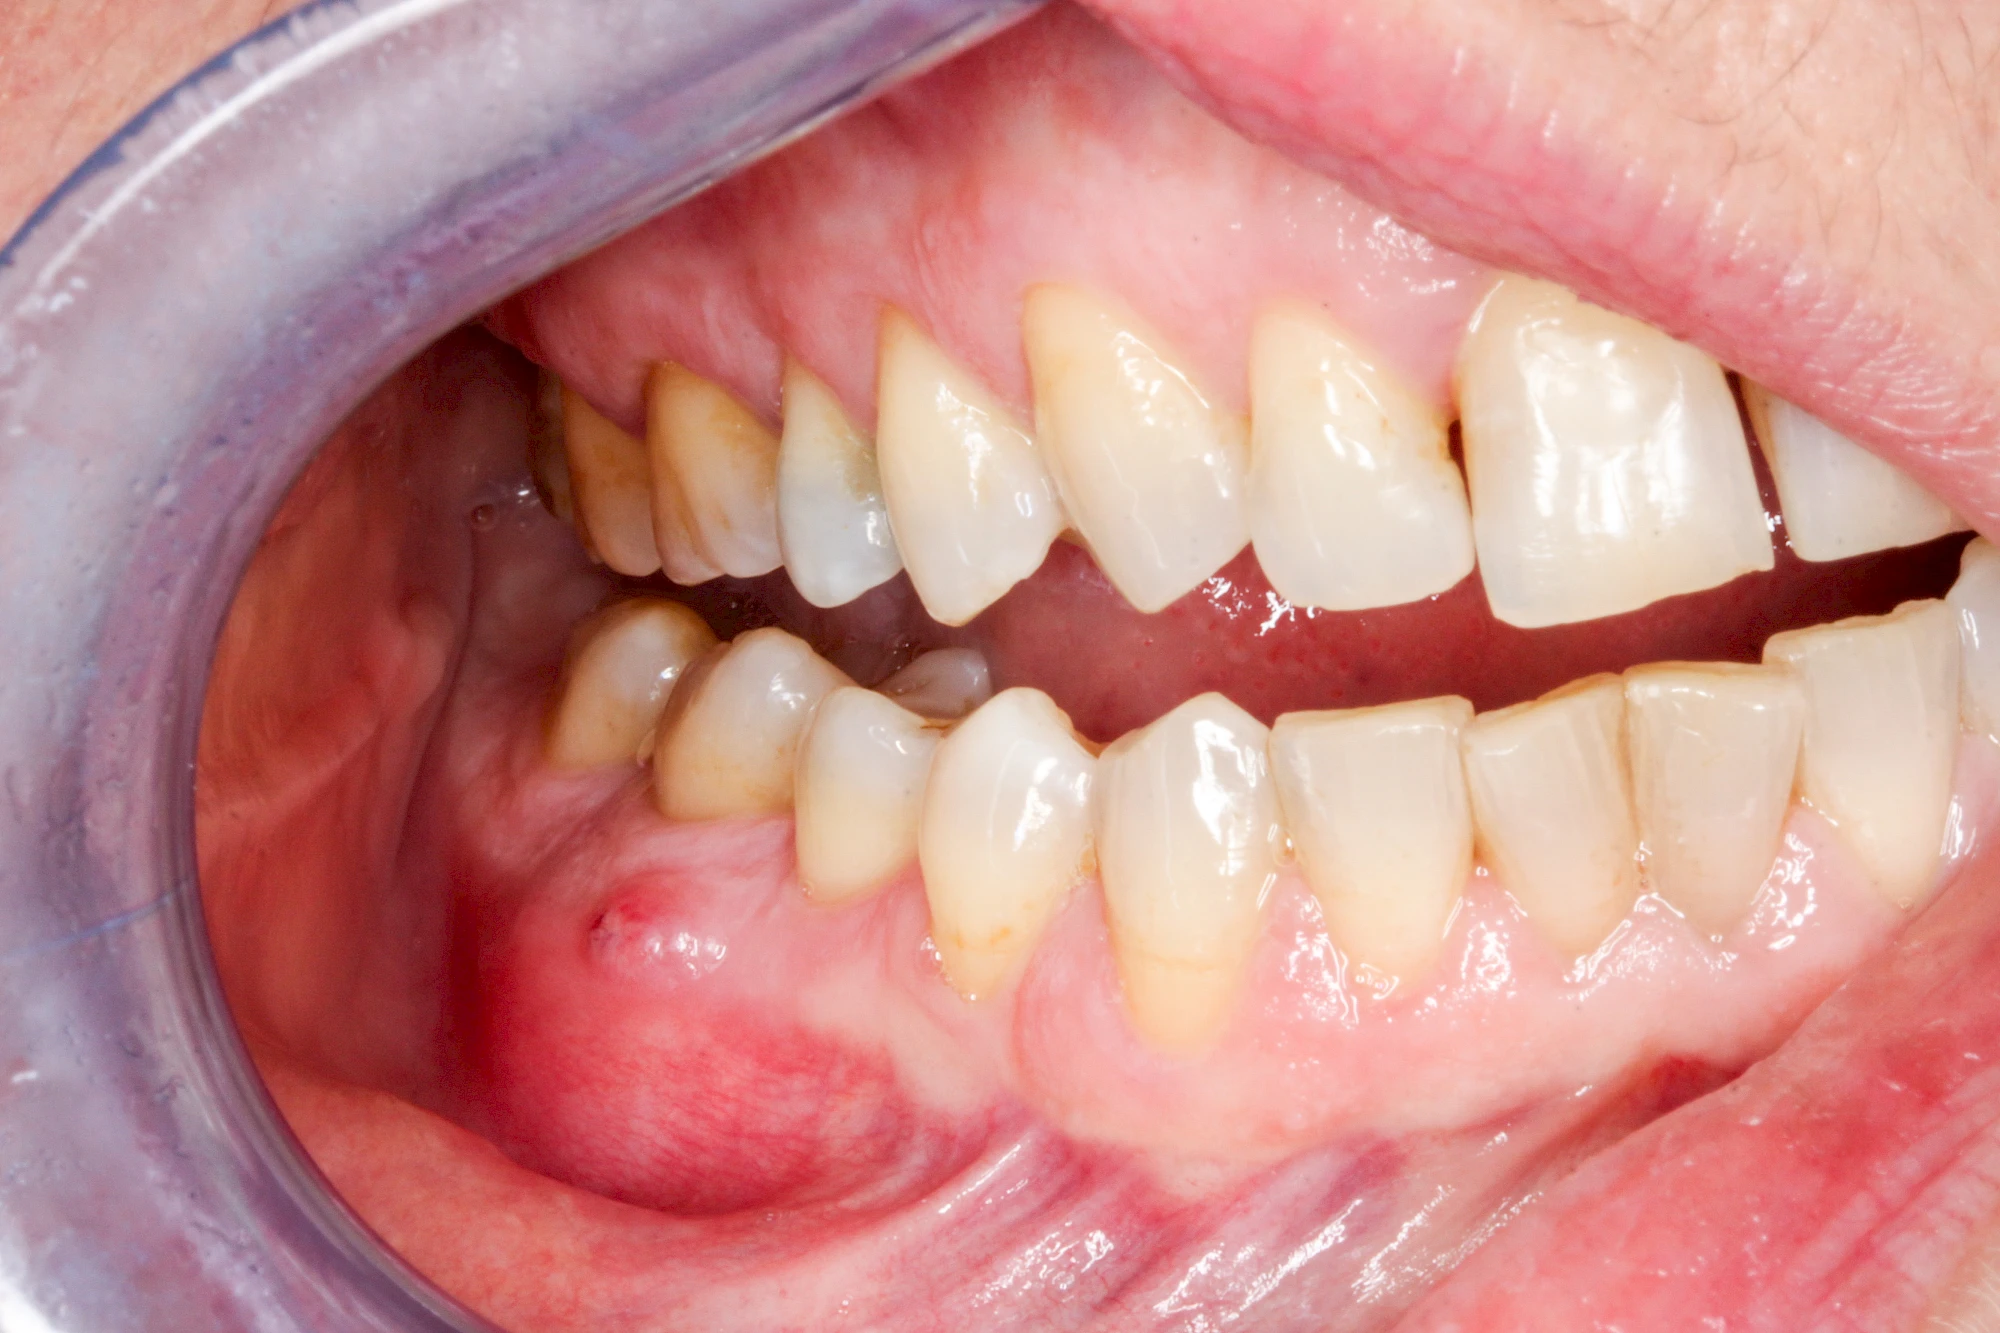

Bei einer Fistel hat sich meist eine Entzündung (manchmal auch Erreger selbst) z. B. aufgrund von Karies oder aufgrund eines Unfalls über den Zahnnerv und die Wurzelspitze (Apex) in den umliegenden Knochen ausgebreitet (apikale Parodontitis) und schnell einen Weg durch den umgebenden Knochen und die aufliegende Schleimhaut in die Mundhöhle gebahnt.

Fisteln sind in der Regel nicht schmerzhaft und fallen häufig als kleine Öffnung weiter entfernt vom Zahnfleisch nahe der Umschlagfalte auf. Aus der Fistelöffnung entleert sich spontan gelbliches Sekret (Eiter) oder es lässt sich mit dem Finger ausstreichen. Manchmal beschreiben die betroffenen Menschen immer wieder einen komischen Geschmack im Mund.

Im fortgeschrittenen Stadium kann die Schleimhaut sich weiter zurückgezogen haben und die Wurzelspitze sichtbar sein. In der Regel treten bei Fisteln keine Schwellungen auf, weil sich die Entzündung nicht im Gewebe ausbreitet.

Bei Fisteln sollte zeitnah der Zahnarzt kontaktiert werden. Treten Fisteln im Zusammenhang mit Schwellungen auf, ist sofort der Zahnarzt zu kontaktieren. Ist der Zahnarzt nicht zu erreichen und es verschlechtert sich der Allgemeinzustand (z. B. Fieber) sollte der Notarzt gerufen werden.